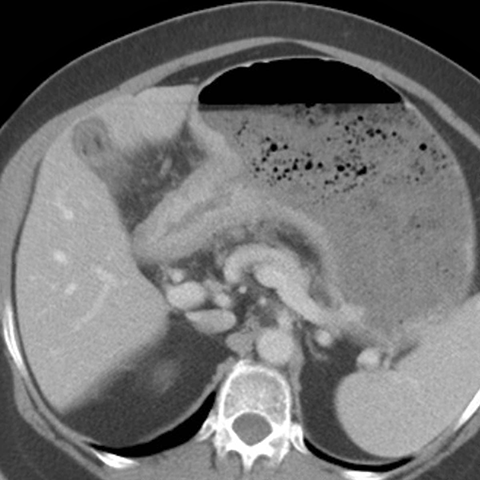

56 year-old male presents with abdominal pain and weight loss [5 of 5]